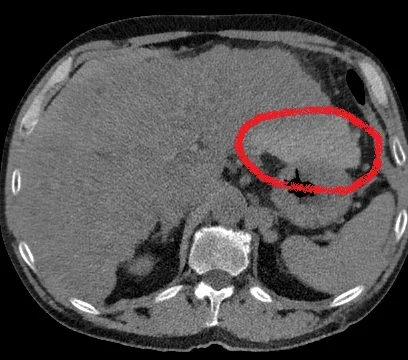

Routine CT shows heterogenous left lobe of liver, with filling defect in left portal vein.

Conventional CT with filling defect in portal vein (yellow arrow)